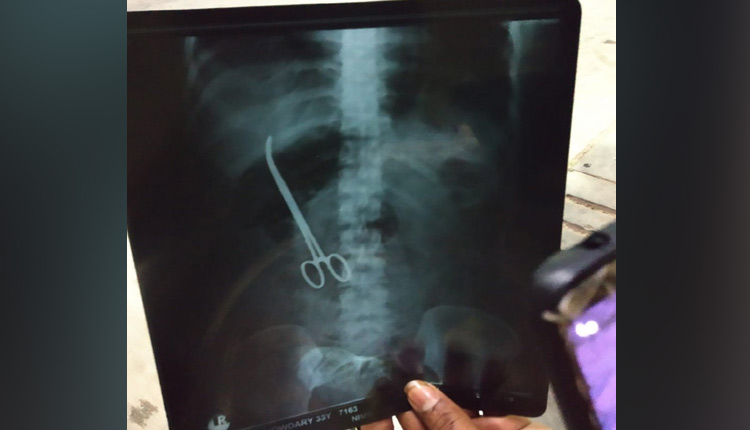

Hyderabad: In a shocking incident, doctors at Nizam’s Institute of Medical Sciences (NIMS) here, left artery forceps in a patient’s abdomen during a surgery.

This negligence by the doctors at the government-run super-speciality hospital came to light Saturday when an X-ray revealed that a pair of forceps was embedded in the stomach of Maheshwari Chowdary.

The 33-year-old had undergone a surgery for hernia November 2 last year. But even after the surgery she complained of severe abdominal pain and an X-ray report revealed that surgeons had accidentally left the surgery tool in her stomach.

The woman is now admitted for another surgery to remove the forceps.